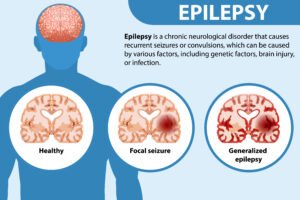

- Epilepsy